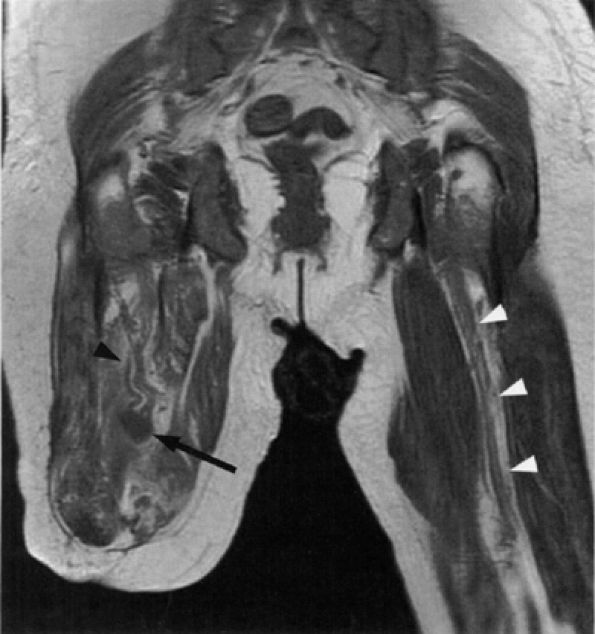

FIGURE 6.15 ● Amputation neuroma. Coronal T1-weighted image demonstrating an amputation neuroma in the right sciatic nerve (arrow). Compare the thickened fascicular pattern of the nerve proximal to the neuroma (black arrowhead) with the normal left sciatic nerve (white arrowheads). (Courtesy of Laercio Rosenberg, MD, Sao Paulo, Brazil)